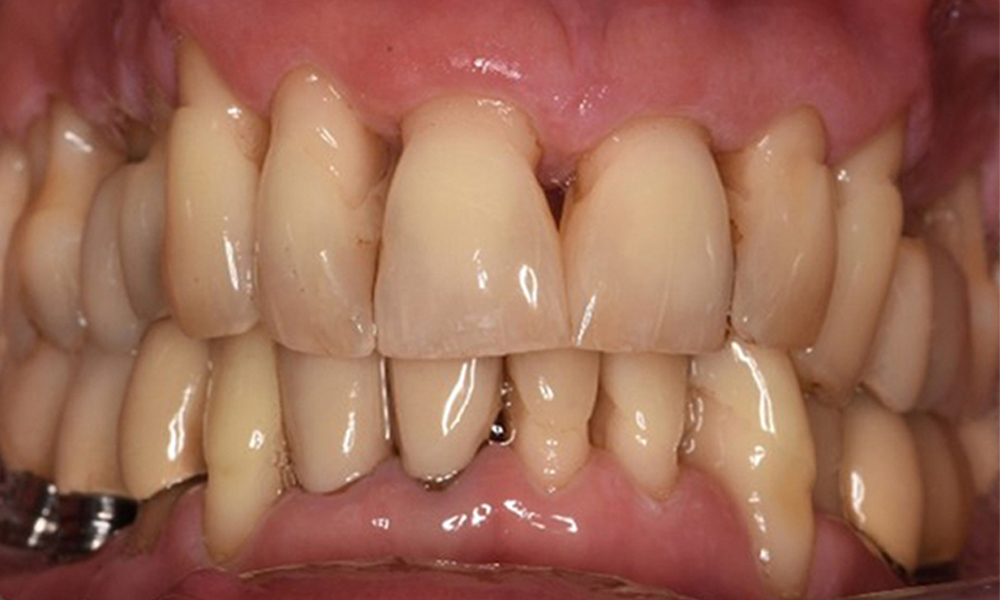

Die Mundhygiene und Mitarbeit des Patienten sind sehr gut (siehe Abbildung "Frontansicht"). Es bedarf lediglich der Reinstruktion und Motivation zum Aufrechterhalten des Mundhygieneverhaltens.

Frontansicht Gebiss (Ober- und Unterkiefer)

Frontansicht